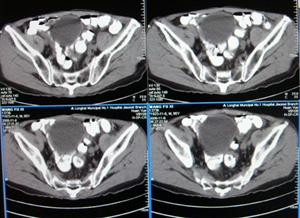

前列腺癌术后10余年,复查有无复发,请指教,图像做得不好,还望包涵

膀胱内可见占位,建议膀胱镜观察

连续看还是前列腺的病变,考虑复发.

前列腺增大,向上突入膀胱内,结合病史考虑前列腺癌复发可能。

图像太小,左侧膀胱壁似见不规则突起,前列腺突入膀胱,建议膀胱镜检查及前列腺增强检查。